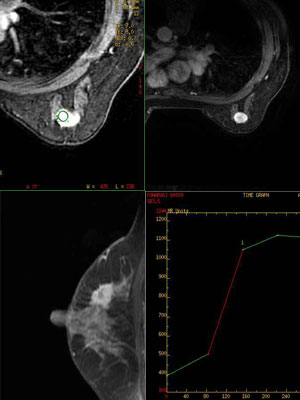

MRI検査

• 各部位に対応できるコイルを多数そろえています

• 全身検査に対応しております

• 特にマンマ(乳腺MRI)、肝臓(プリモビストEOB)に力を入れています

• ご紹介時には、PDFの書面に記載頂き来院ください

MRI画像マンモ